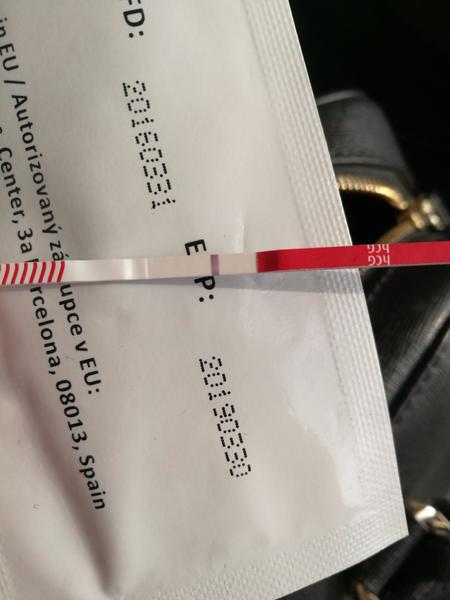

ahojte babule, mam taku otazku...mate skusenost ze pocas 3 dni vam nesilnela druha ciarka na teste ale bola rovnaka???ako duch????

@lenusa20 ahoj, ten posledný test je podľa mňa chybný. Nie je možné aby si po štyroch testoch ktoré krásne silneli zrazu mala čistý test. Okrem toho tieto testy (ten posledný) robí kanáliky dievčatám ktoré tehotné niesu.. Za mňa by som ti odporučila obyčajný pepino test, alebo v tescu predávajú také úplne lacné testy sú citlivosť 25ml ale za mňa odporučujem alebo potom rovno digi test clearblue, ktorý ti ukáže aj dobu od oplodnenia. Veľa šťastia a krásne // čiarky prajem 😊

@zuzuliena1 @nivea777 Ten 10 je teraz pred polhodinou robeny. Mne tiez hlava nekapca, ze 20tkove uz naznacovali od 8DPO a 10tkovy hoci teraz robeny a zrazu nic!!! Skusim zajtra rano este a uvidim ci ta mrcha nakoniec nepride...a uvidim co sa bude diat do piatku a ked nic, tak skocim k dr. na vysetrenie :/

@tshirt aj mne sa to javí ako dúšik, testuj z ranneho mocu alebo skus az o 2 dni.